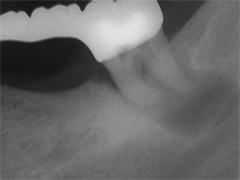

Einlage erneut rein. Als es dann 4 Wochen später bei der hinteren Wur­zel aussen anzuschwellen begann und ein Medikamentenwechsel ohne Wir­kung blieb, wurden die hinteren Ka­näle abgefüllt und auch in gleicher Sitzung das überstopfte Material (Bild 1) mittels Resektion (Bild 2) von aussen entfernt.

Die ersten beiden Aufnahmen sind aus dem Jahr 1999, die 3. von 2006